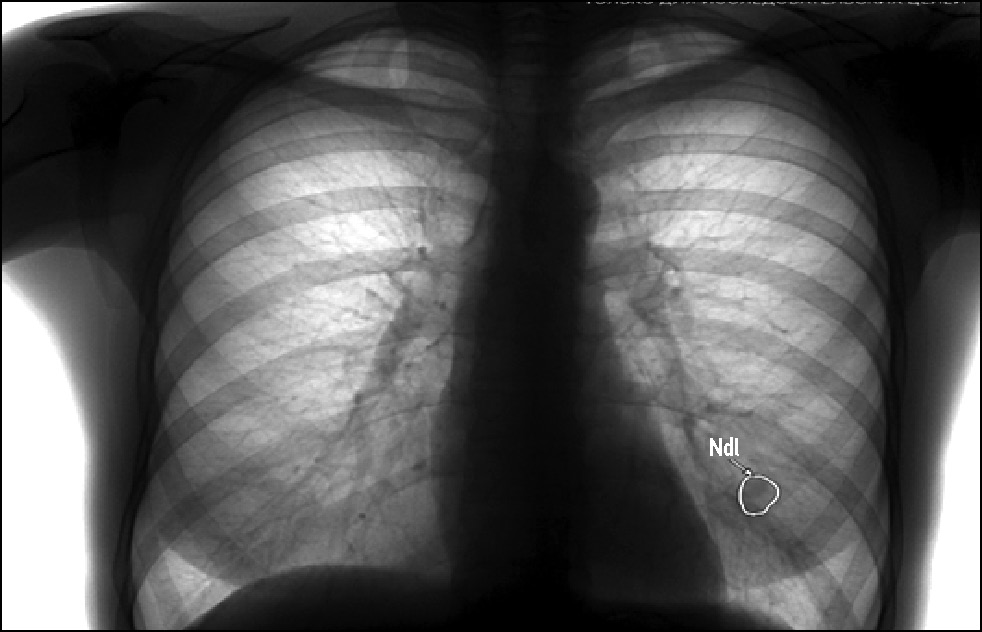

Стоит отметить вероятность наличия теней дополнительных мягкотканных, в том числе кожных образований, уплотнений и сосков молочных желёз, проецирующихся на рентгеновское изображение лёгких, которые могут быть ошибочно интерпретированы ПО на основе ТИИ как лёгочные образования, и требующих пересмотра врачом [22, 23]. В рамках данного исследования был выявлен один ложноположительный случай срабатывания ПО на основе ТИИ, связанный с выраженной подкожно-жировой клетчаткой (рис. 5), а также один случай, когда ИИ-сервис принял тень соска за лёгочный узел (рис. 6).

Рис. 6. Тень соска молочной железы, ошибочно маркированная как лёгочный узел.